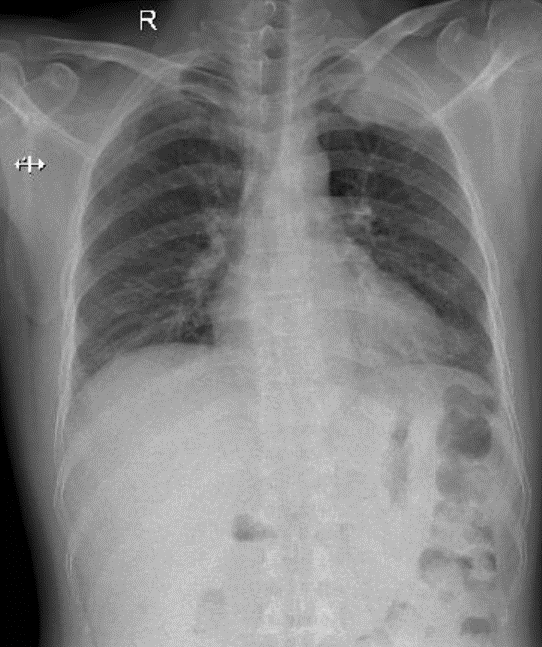

Hãy phân tích tình huống nam 45 tuổi

1-U đỉnh phổi trái (Pancoast tumor) 2-dày thất trái